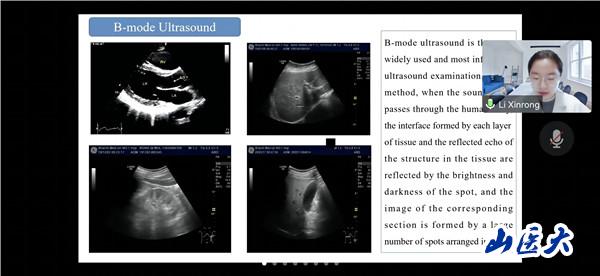

会议期间,俄罗斯沃罗涅日国立医科大学的三名学生代表分享了超声医学的演进历史,现代超声成像技术及容积超声诊断技术相关知识。万象城第一医院高峰、第二医院王倩和医学影像学院李欣榕采用丰富的病例和图像展示了超声影像技术在肾功能疾病、脑颈动脉疾病和甲状腺疾病诊断和治疗中的应用。与会师生认真聆听、积极思考、踊跃提问,营造了学术思想碰撞、技术方法借鉴、疑难问题共析的浓厚氛围。